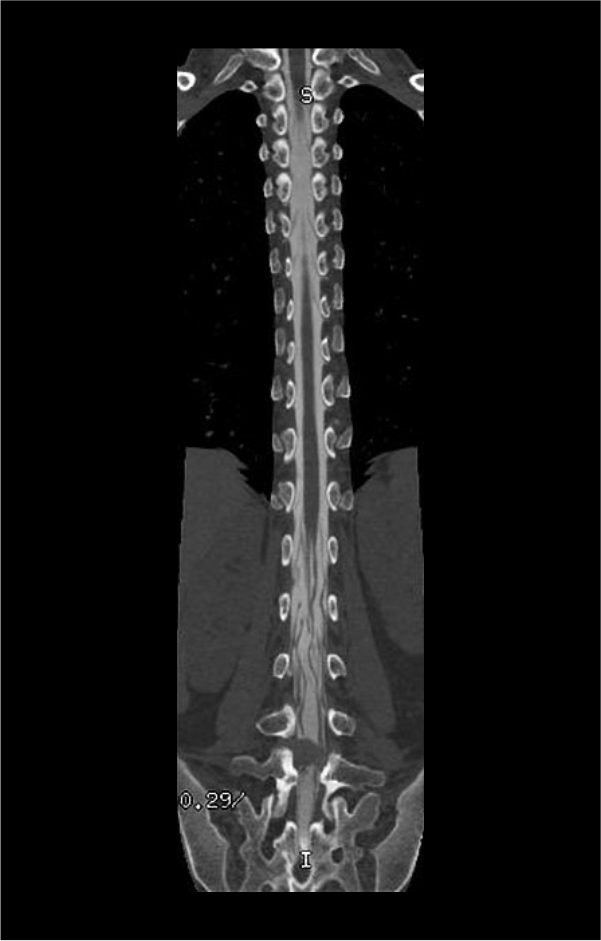

- Sagittal and coronal images with ≤ 2 mm slice thickness in bone window (WW: 3500, WL: 350).

- Contagious axial slices in bone window and soft-tissue window (WW:500, WL:50) with ≤ 2mm and ≤ 3mm slice thicknesses respectively.

- Axial images through inter-vertebral disk for the assessment of spinal cord compressions.